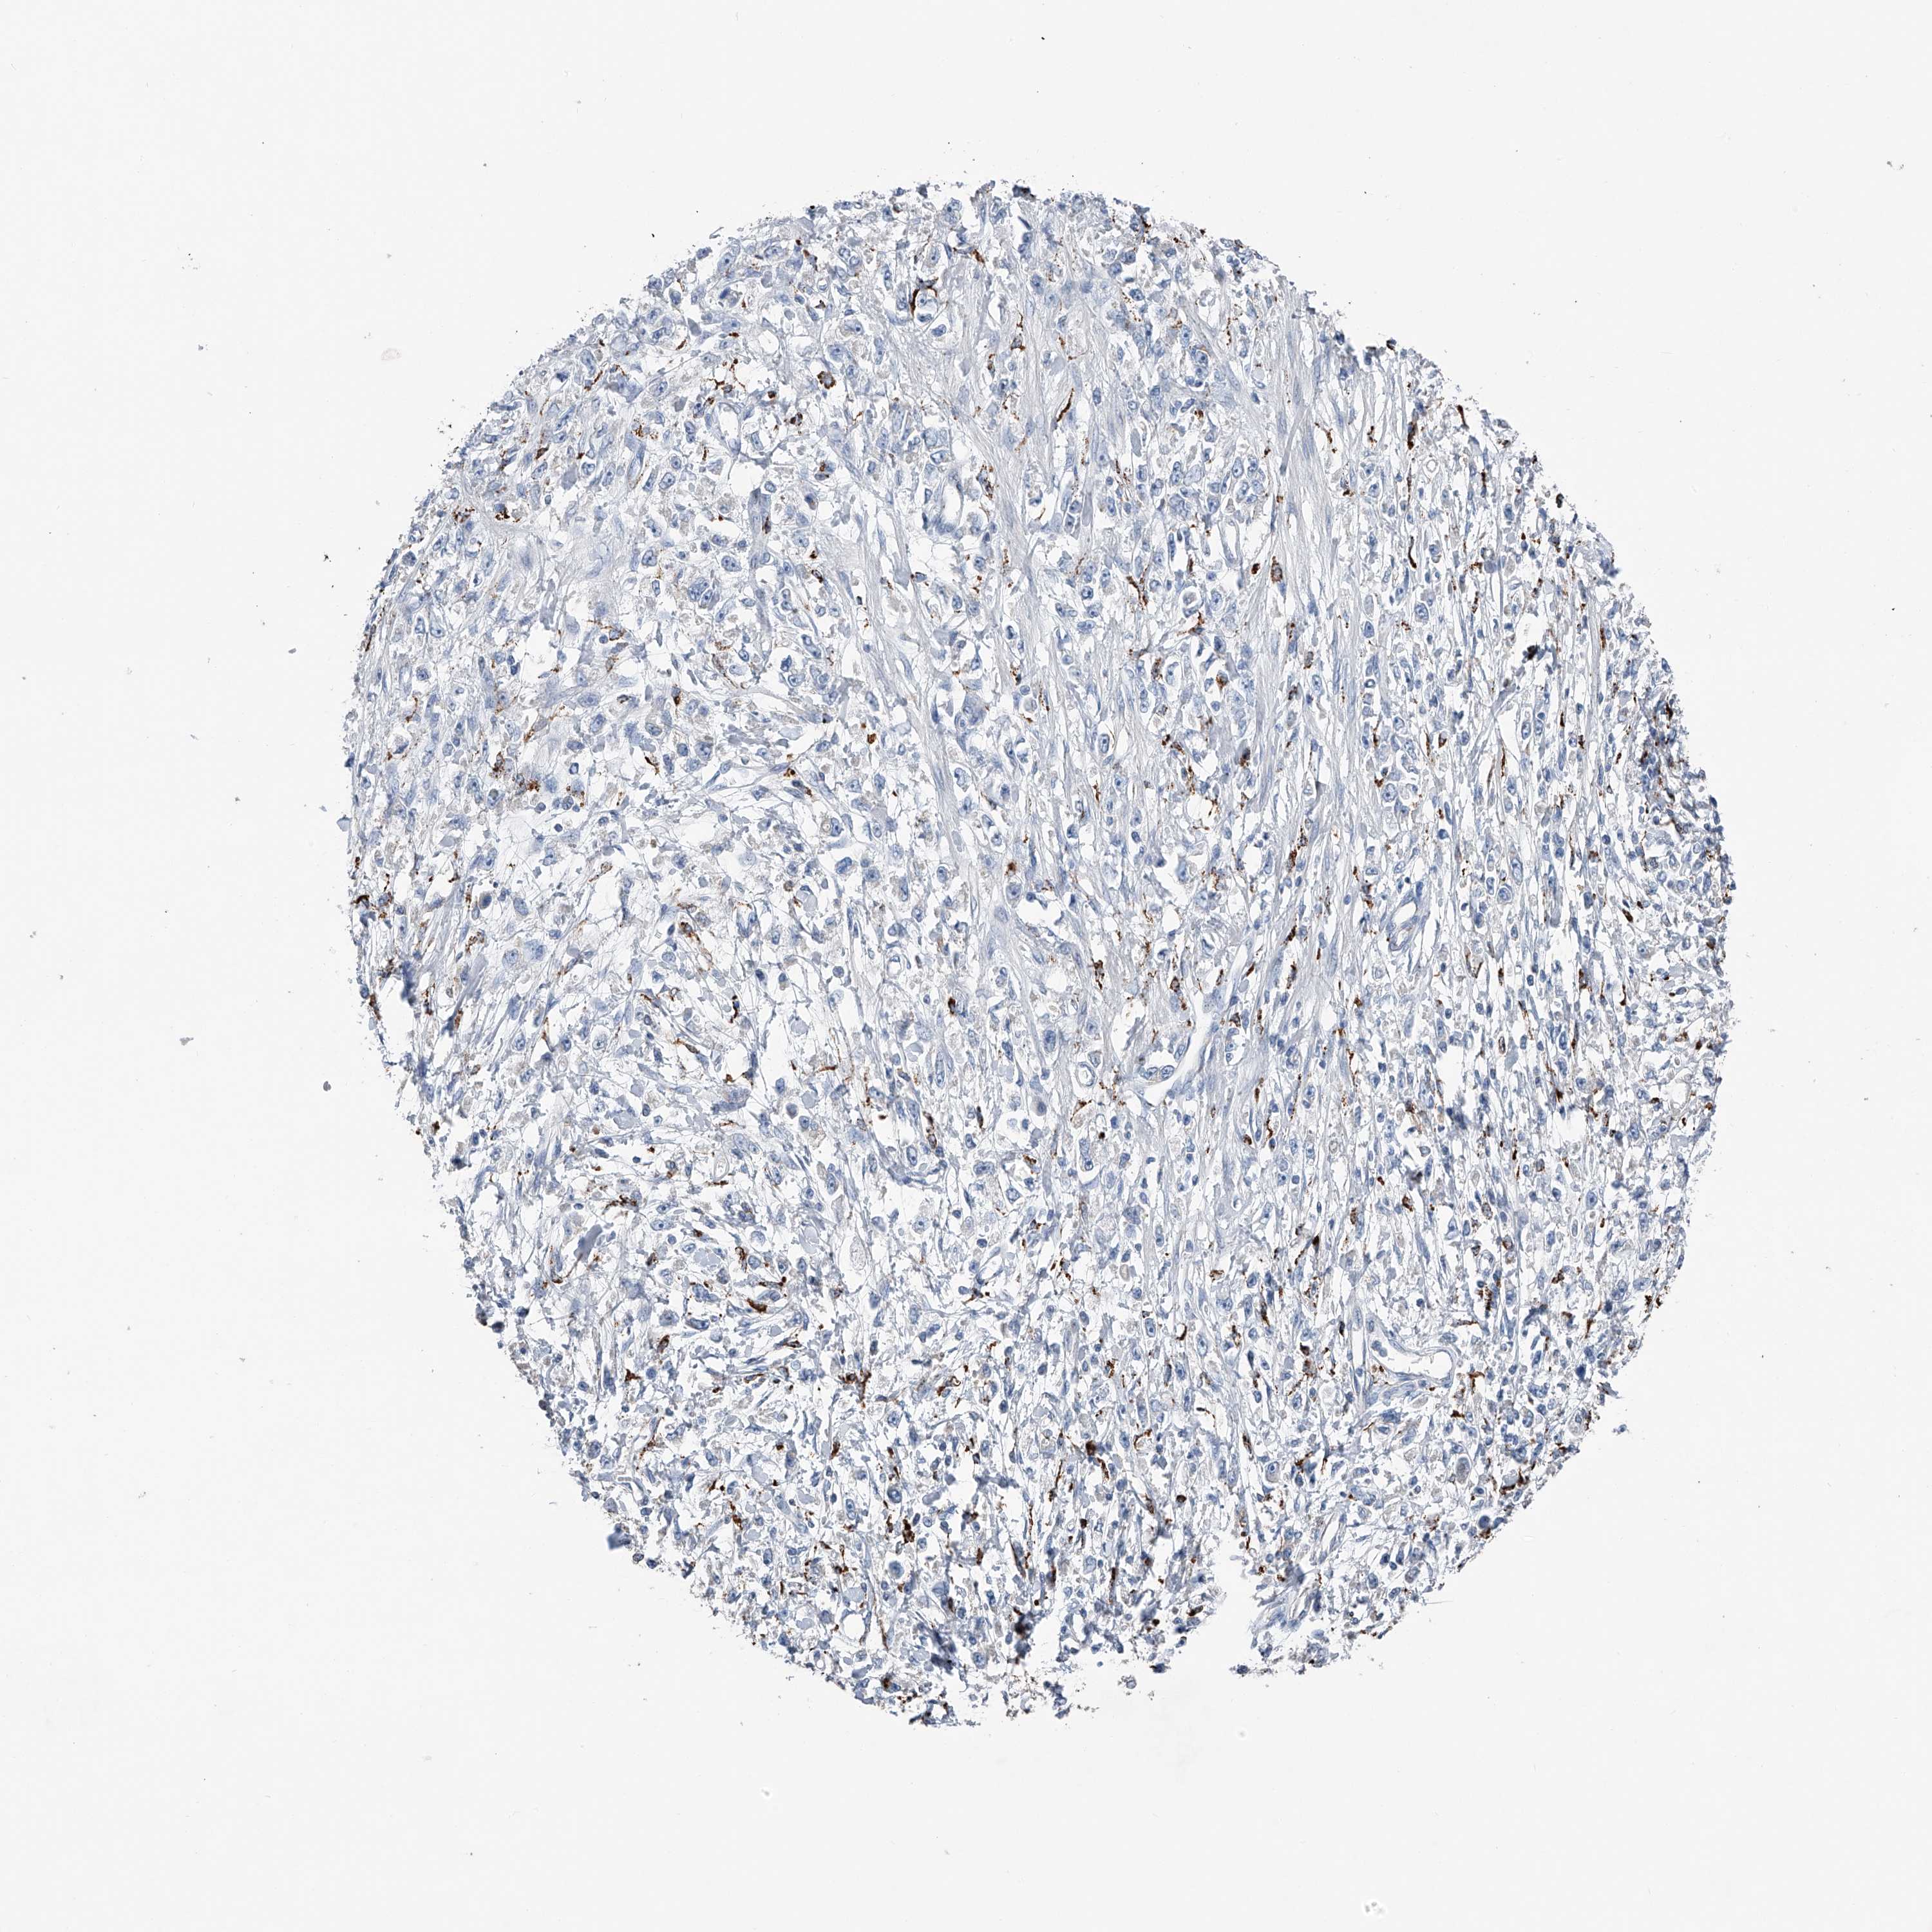

STOMACH CANCER - Protein expressioni

A mouse-over function shows sample information and annotation data. Click on an image to view it in a full screen mode. Samples can be filtered based on level of antibody staining by selecting one or several of the following categories: high, medium, low and not detected. The assay and annotation is described here.

Note that samples used for immunohistochemistry by the Human Protein Atlas do not correspond to samples in the TCGA dataset.

Antibody stainingi

Antibody staining in the annotated cell types in the current human tissue is reported as not detected, low, medium, or high, based on conventional immunohistochemistry profiling in selected tissues. This score is based on the combination of the staining intensity and fraction of stained cells.

Each image is clickable and will lead to virtual microscopy that enables deeper exploration of all samples and also displays staining intensity scores, fraction scores and subcellular localization as well as patient and tissue information for each sample.

Antibody HPA031312

Staining

High

Medium

Low

Not detected

Intensity

Strong

Moderate

Weak

Negative

Quantity

>75%

75%-25%

<25%

None

Location

Nuclear

Cytoplasmic/membranous

Cytoplasmic/membranous,nuclear

Adenocarcinoma, NOS